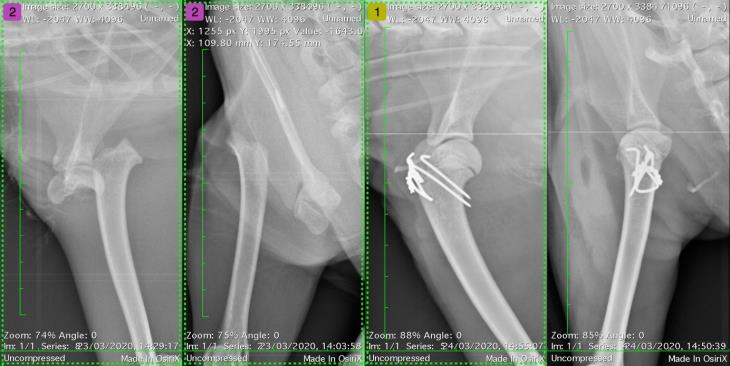

A proximal dorsal intertarsal instability at the talocentral (or proximal intertarsal) joint was also identified, an interesting injury and one uncommon to see without other concurrent tarsal injuries. The ruptured dorsal ligaments are not in tension during weight bearing, which explains why Max was able to ambulate so well in spite of a serious and significant injury. This highlights the importance a full examination in all patients, especially those who have been unfortunate enough to sustain trauma.

Max underwent surgery to repair his physeal fracture with pins and a tension band. A dorsal mini plate was placed across the dorsal tarsus with two screws in the talus, one in the central tarsal bone, one in the third tarsal bone and one in the very proximal second metatarsal bone.